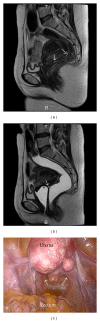

Objective: We conducted a single-center study to evaluate the usefulness of the magnetic resonance (MR) imaging jelly method for diagnosing endometriosis-associated adhesions in the Pouch of Douglas.

Methods: Thirty women with menstrual pain, dyspareunia, and chronic pelvic pain were enrolled in the study. All had been scheduled for laparoscopic surgery on the basis of pelvic and/or ultrasonographic (US) evaluation. All underwent MR imaging both with and without application of US jelly to the vagina and rectum. The images were compared and analyzed postsurgically in a random and blinded fashion by a radiology specialist and a radiology fellow. The radiologists' interpretations of the images were compared to the surgical findings recorded on DVDs.

Results: Adhesions in the Pouch of Douglas were found in 21 patients. The sensitivity and specificity of MR imaging without jelly administration were 85.7% and 55.6%, respectively, for the specialist and 81.0% and 55.6%, respectively, for the fellow; with jelly administration, values were 95.2% and 88.9% for the specialist and 90.5% and 66.7% for the fellow. Opacity produced by the jelly increased the sensitivity and specificity for both radiologists.